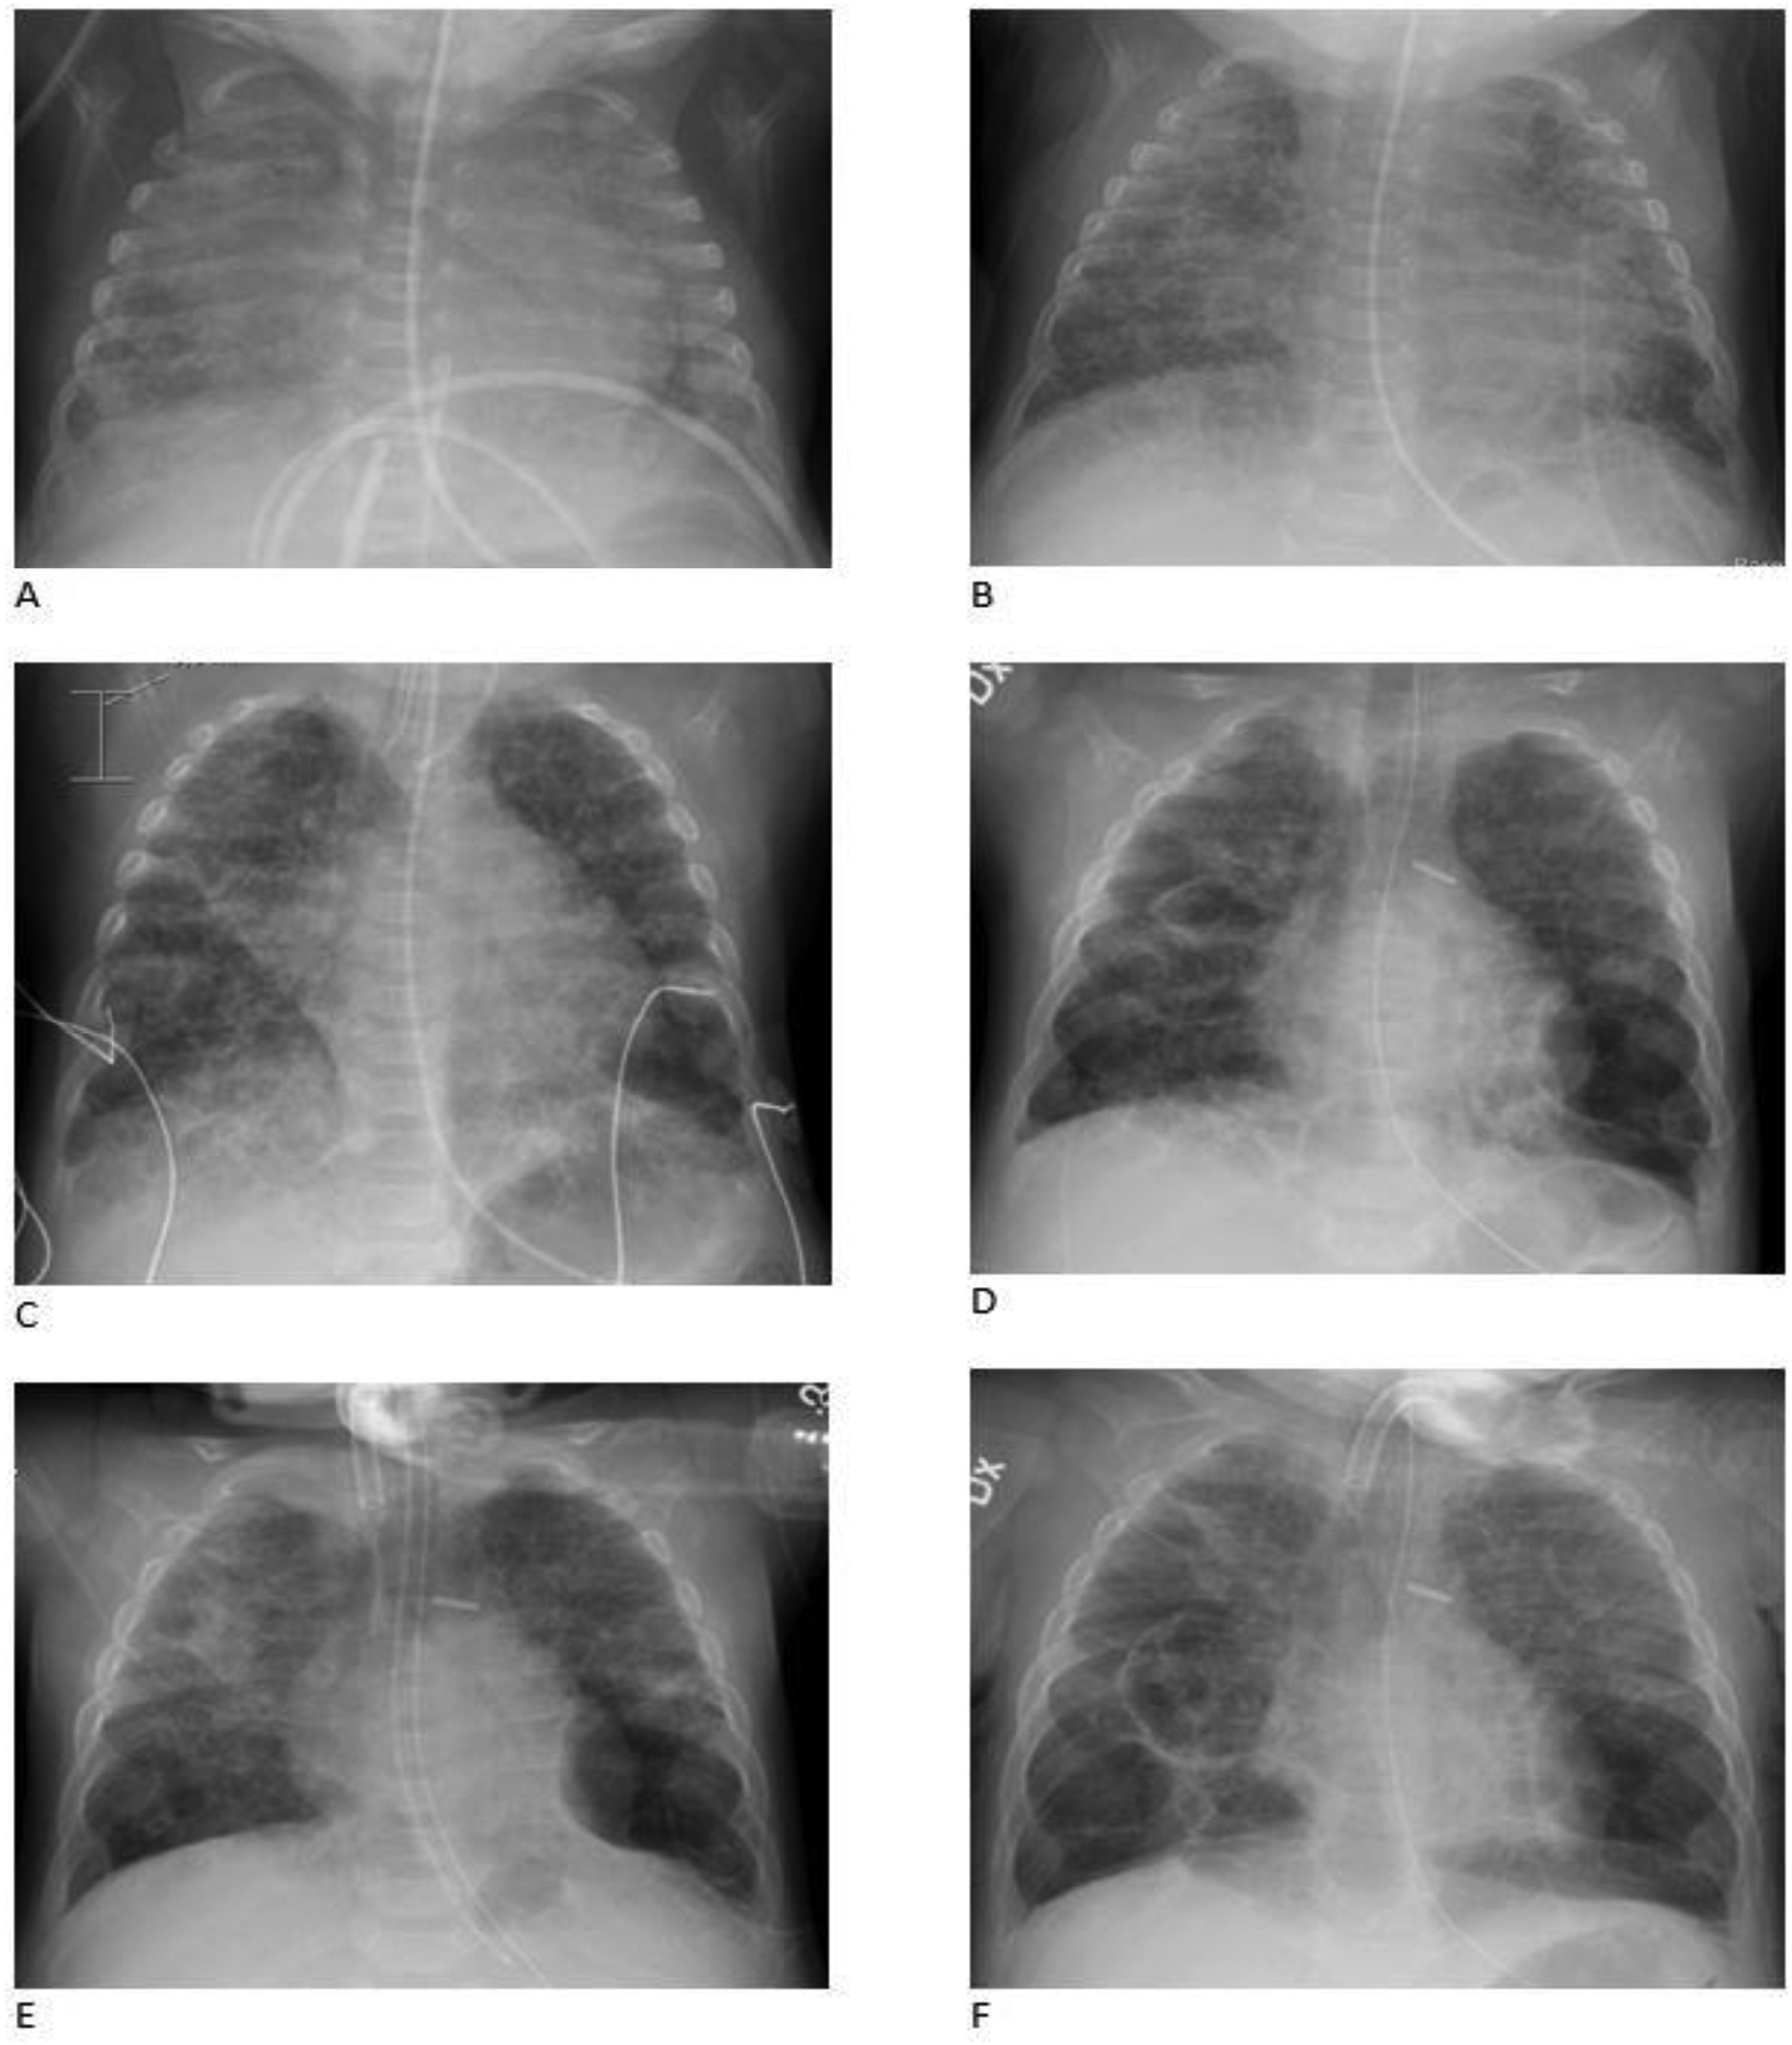

Figure 1

Representative chest radiographs. (A) PMA (post-menstrual age) 26w, (B) PMA 35w, (C) PMA 41w (before closure of the shunts), (D) PMA 50w (before tracheostomy), (E) PMA 55w (after tracheostomy) and (F) PMA 56w. The child developed early bilateral fine granular opacities in the pulmonary parenchyma and air bronchograms as seen in respiratory distress syndrome (RDS). Pulmonary edema could not be excluded. The granular opacities remained and became coarse. Hyperinflation and cystic changes developed and the cystic structure in left lower lobe was defined as pneumatocele. Transient apical atelectasis and non-specific parenchymal opacities occurred mainly on the right side.

A significant rise in the systolic and diastolic arterial blood pressure [mean arterial pressure (MAP) ≥90–105 mm Hg] occurred postoperatively. Cardiac ultrasounds showed sign of a remaining sub-systemic PH after the correction and a decision was made to start sildenafil treatment on the third postoperative day aiming at a target dose of 2 mg/kg/day. Repeated cardiac ultrasounds during the treatment with sildenafil demonstrated a persistent PH at sub-systemic levels evaluated by the tricuspid regurgitant pressure gradient (75 mm Hg, 4 m/s). There was no sign of right ventricular failure. The contractility and the systolic function of the left ventricle were described as good. MAP remained high (> 70–80 mm Hg), when the child was awaken for several weeks after the correction. A diagnosis of severe BPD was confirmed based on chest x-ray ( Figure 1 ) and the definition by the National Institute of Child Health and Human Development program ( 36, 37). A cystic structure in left lower base was seen on the chest x-ray already the day after birth and it was later defined as a congenital pulmonary adenomatoid malformation (CPAM). Emphysematous changes developed after 35 weeks of postmenstrual age (PMA) (Figure 1). The infant required continuous non-invasive ventilator support using a full face mask and oxygen supplementation with FiO2 of 0.5–0.75 to maintain oxygen arterial saturations between 65% and 85%. Despite receiving a sildenafil dose of 1.9 mg/kg/day, the baby developed cyanotic spells with dangerously low to undetectable levels of oxygen saturation and was claimed to have untreatable PH with repeated pulmonary hypertensive crises. It was difficult to increase her feeding due to gastric retentions and what was judge as abdominal spasm or pain. Broad-spectrum antibiotic treatments were given due to the growth of MRSA, and Klebsiella pneumoniae in the upper airways, and rhinovirus was also detected (Table 1).